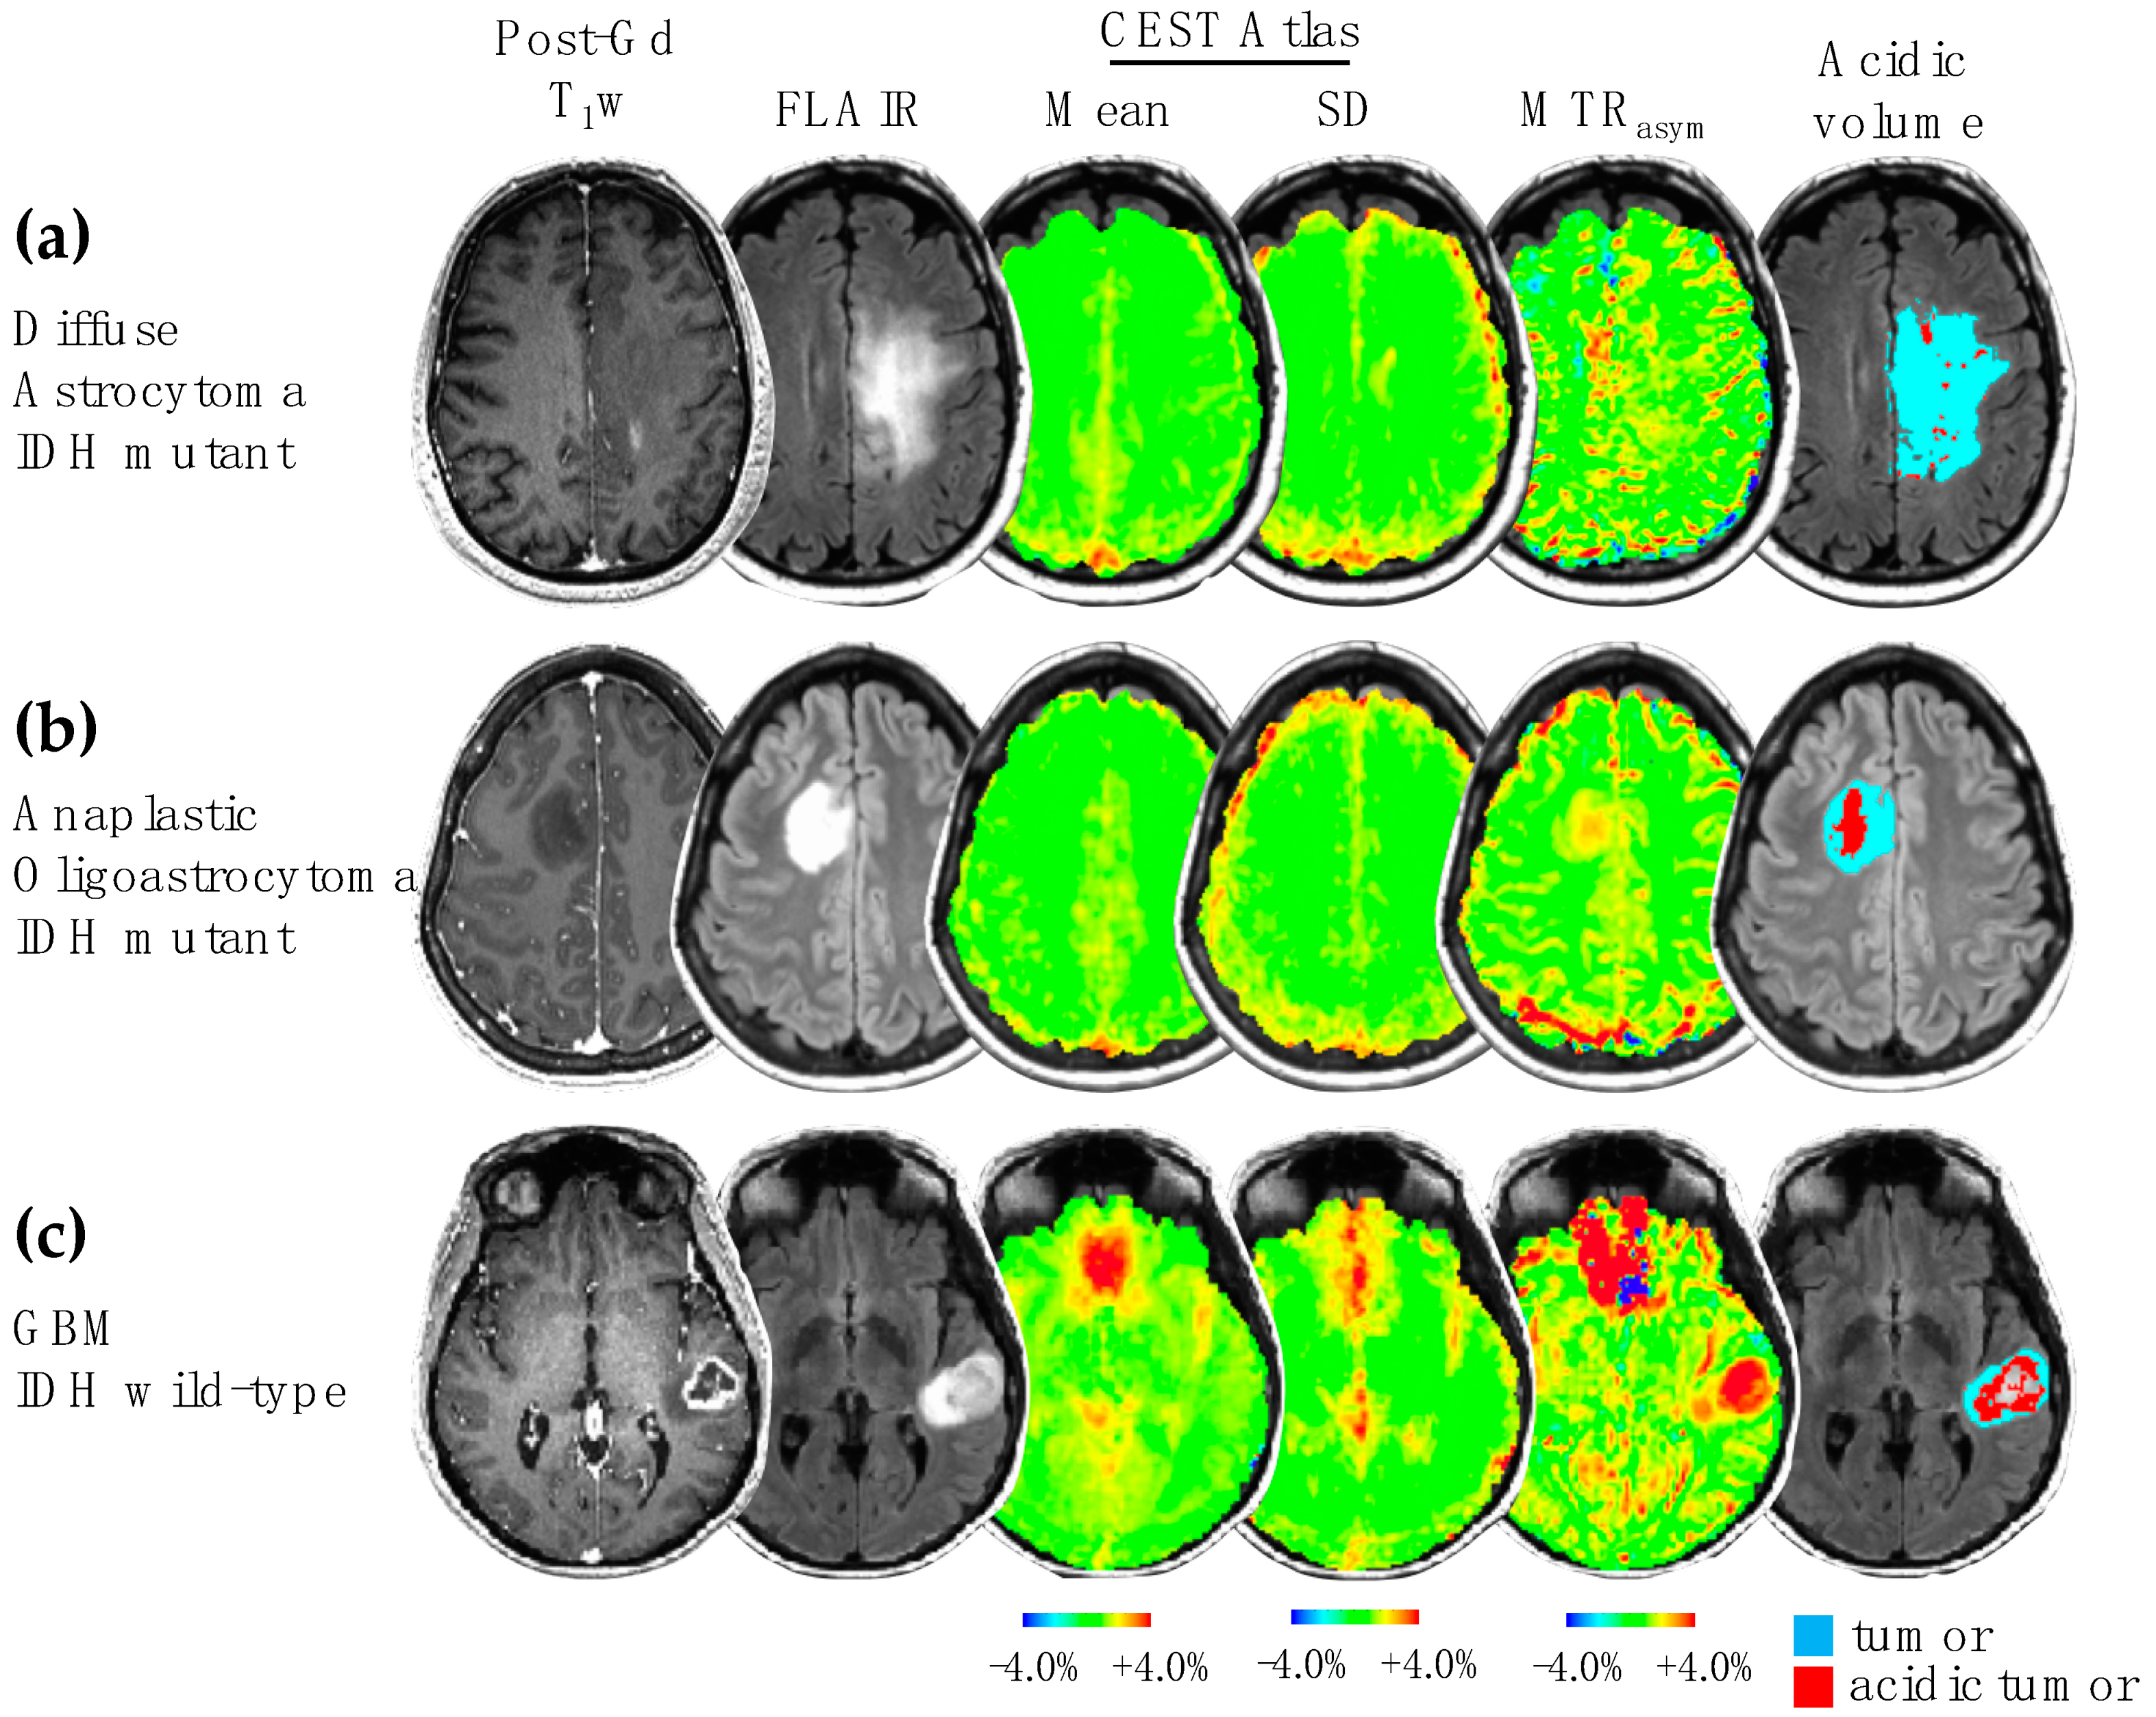

3.1. Acidity and Hypoxia in IDH Mutant and Wild-Type Gliomas